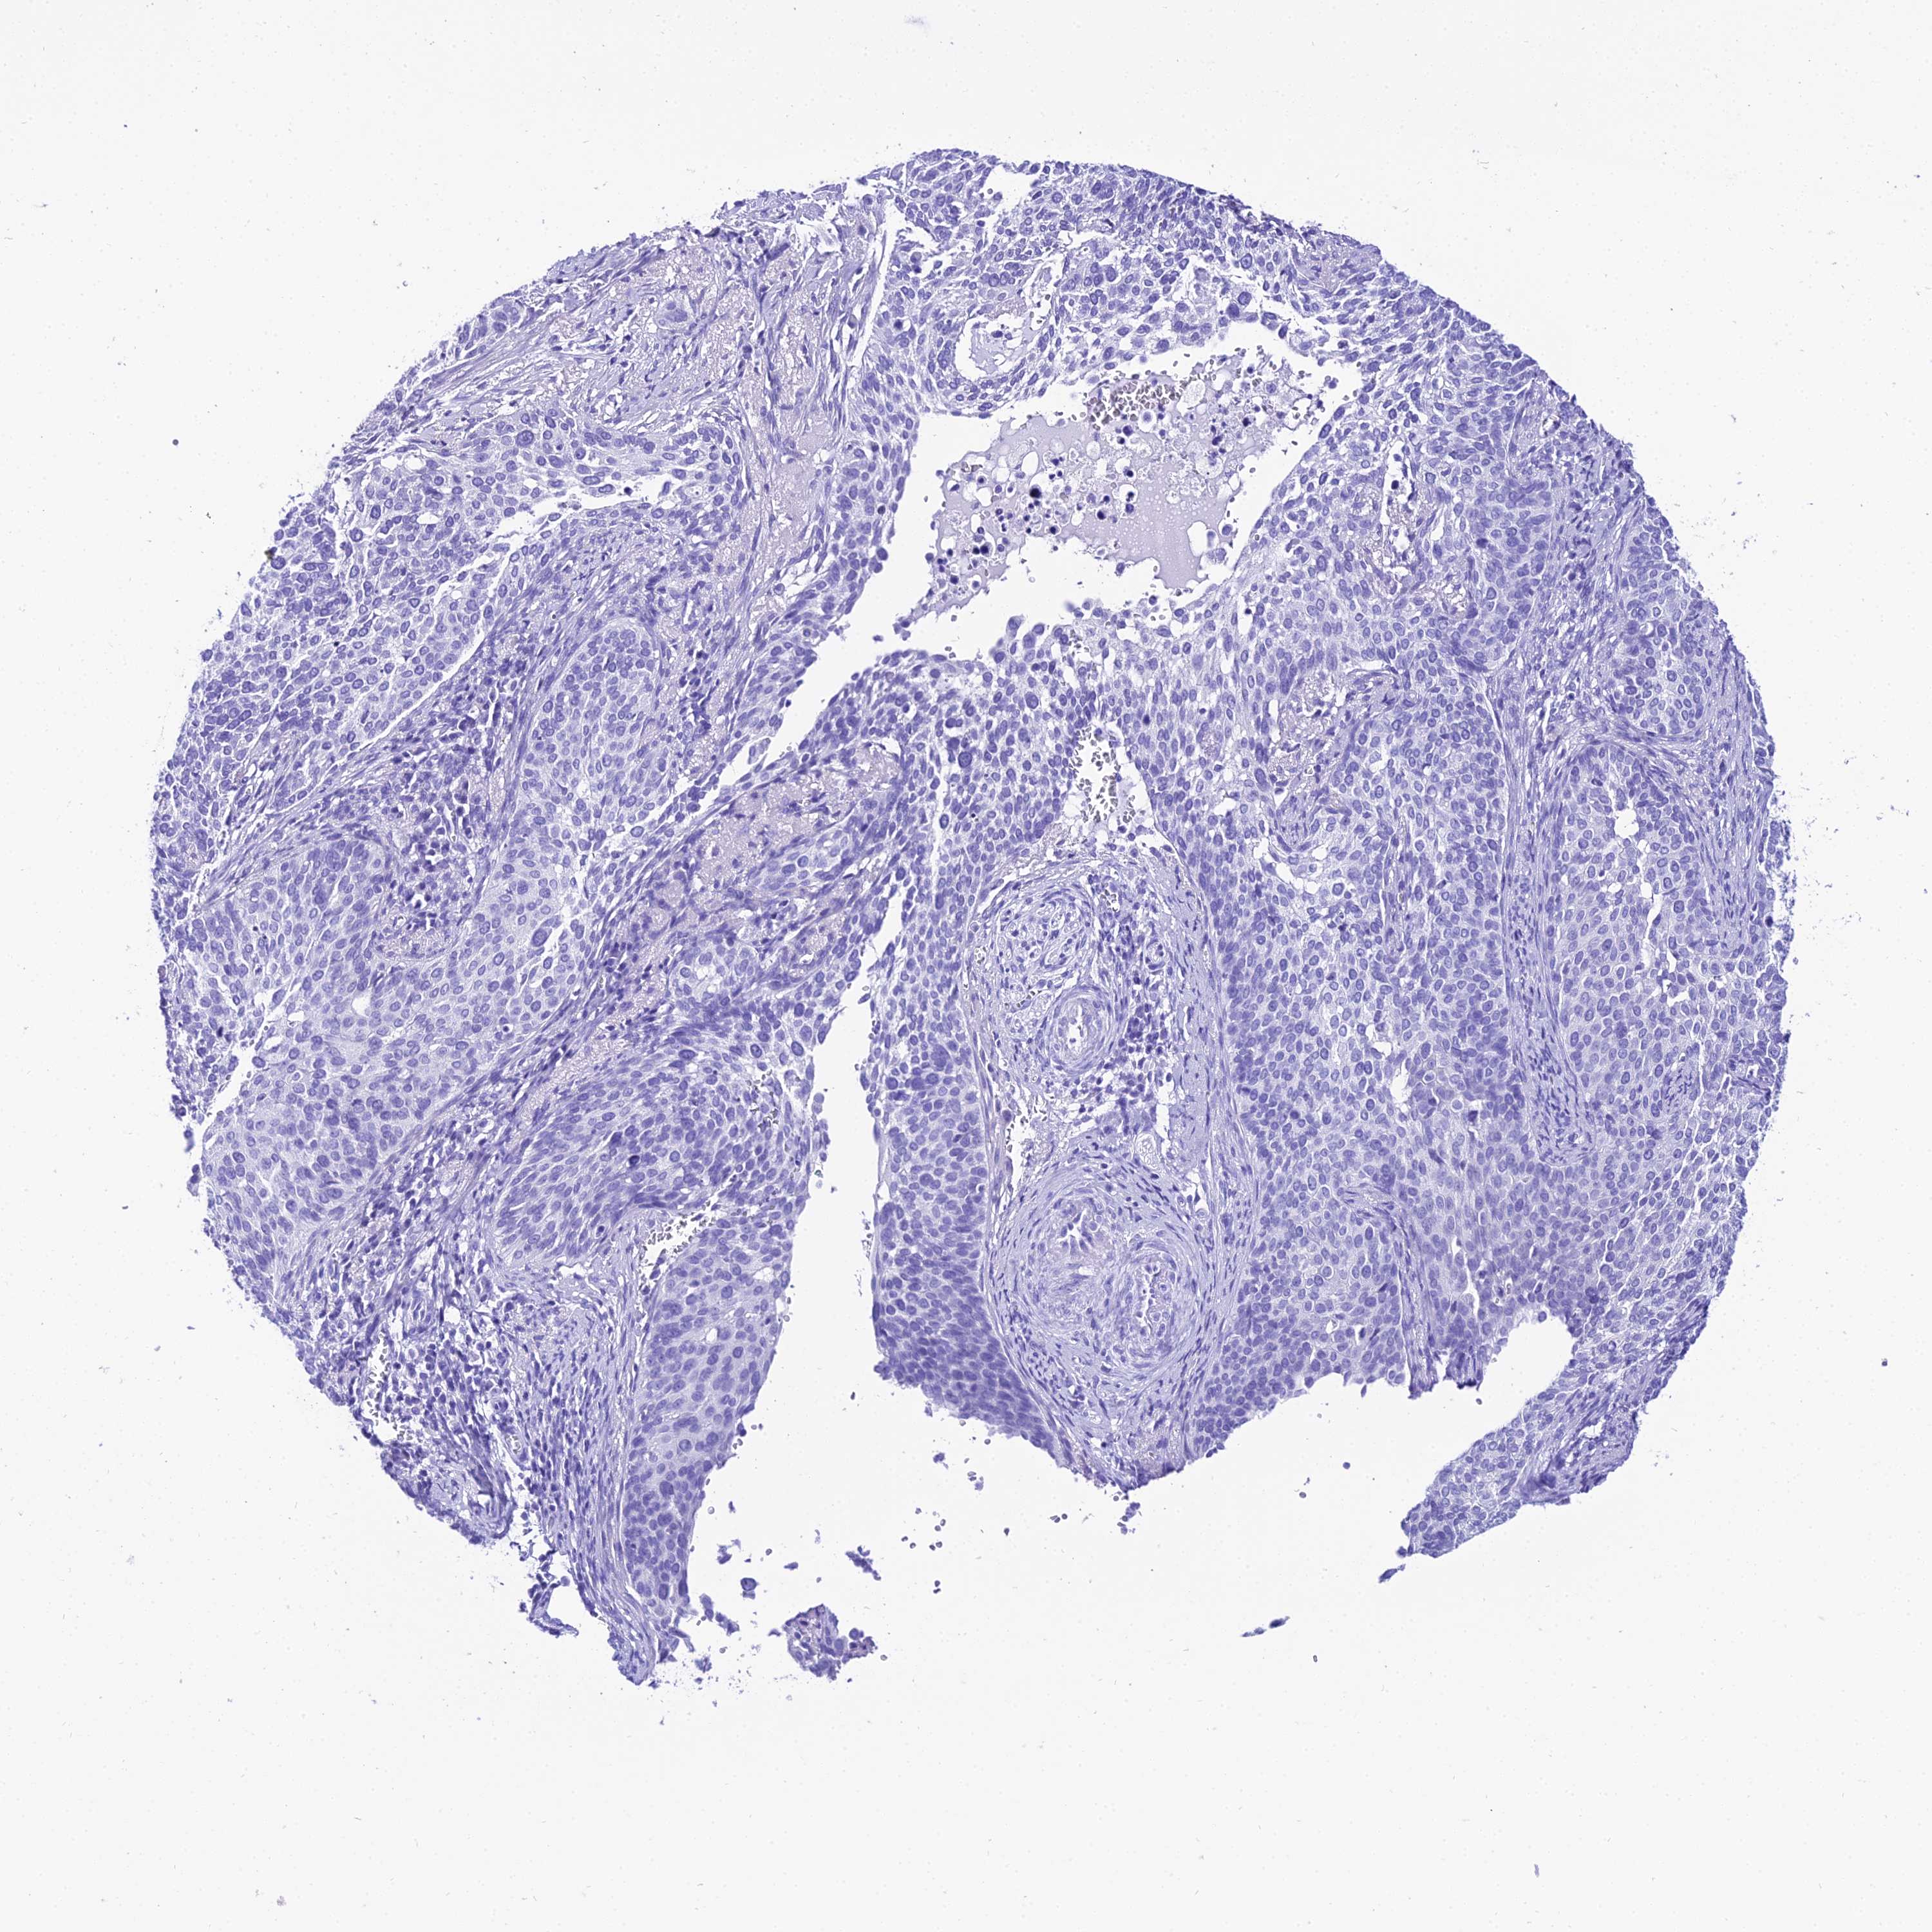

CERVICAL CANCER - Protein expressioni

A mouse-over function shows sample information and annotation data. Click on an image to view it in a full screen mode. Samples can be filtered based on level of antibody staining by selecting one or several of the following categories: high, medium, low and not detected. The assay and annotation is described here.

Note that samples used for immunohistochemistry by the Human Protein Atlas do not correspond to samples in the TCGA dataset.

Antibody stainingi

Antibody staining in the annotated cell types in the current human tissue is reported as not detected, low, medium, or high, based on conventional immunohistochemistry profiling in selected tissues. This score is based on the combination of the staining intensity and fraction of stained cells.

Each image is clickable and will lead to virtual microscopy that enables deeper exploration of all samples and also displays staining intensity scores, fraction scores and subcellular localization as well as patient and tissue information for each sample.

Antibody HPA045461

Staining

High

Medium

Low

Not detected

Intensity

Strong

Moderate

Weak

Negative

Quantity

>75%

75%-25%

<25%

None

Location

Nuclear

Cytoplasmic/membranous

Cytoplasmic/membranous,nuclear

Squamous cell carcinoma, NOS

Adenocarcinoma, NOS